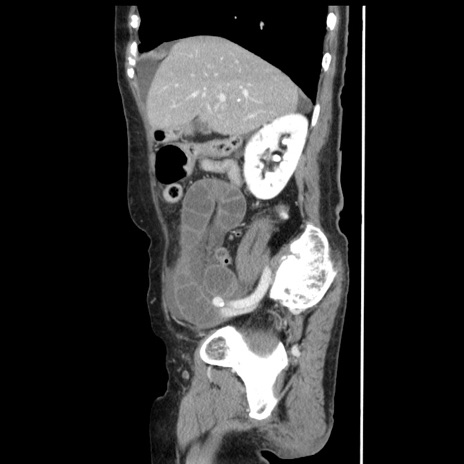

症例1(矢状断像)

【症例】80歳代女性

【主訴】腹痛

【現病歴】8時間前から腹痛あり来院。

【既往歴】糖尿病、脂質異常症、子宮体癌にて子宮全摘術

【身体所見】意識清明・会話良好だが腹痛で苦悶様、全腹部にわたって反跳痛と圧痛あり

【データ】WBC 13600、CRP 0.14、LDH 224、CK 90

冠状断像